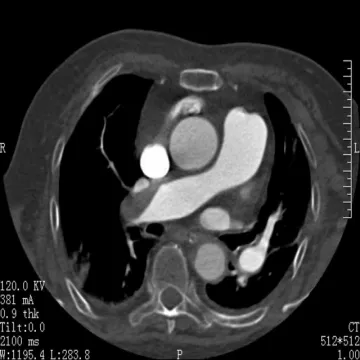

②影像学检查:CT肺动脉造影(CTPA)扫描速度快,图像可以多方位重建,能清晰显示血栓位置,是确诊肺动脉栓塞常用的方法。影像表现如图所示:

右肺动脉栓塞